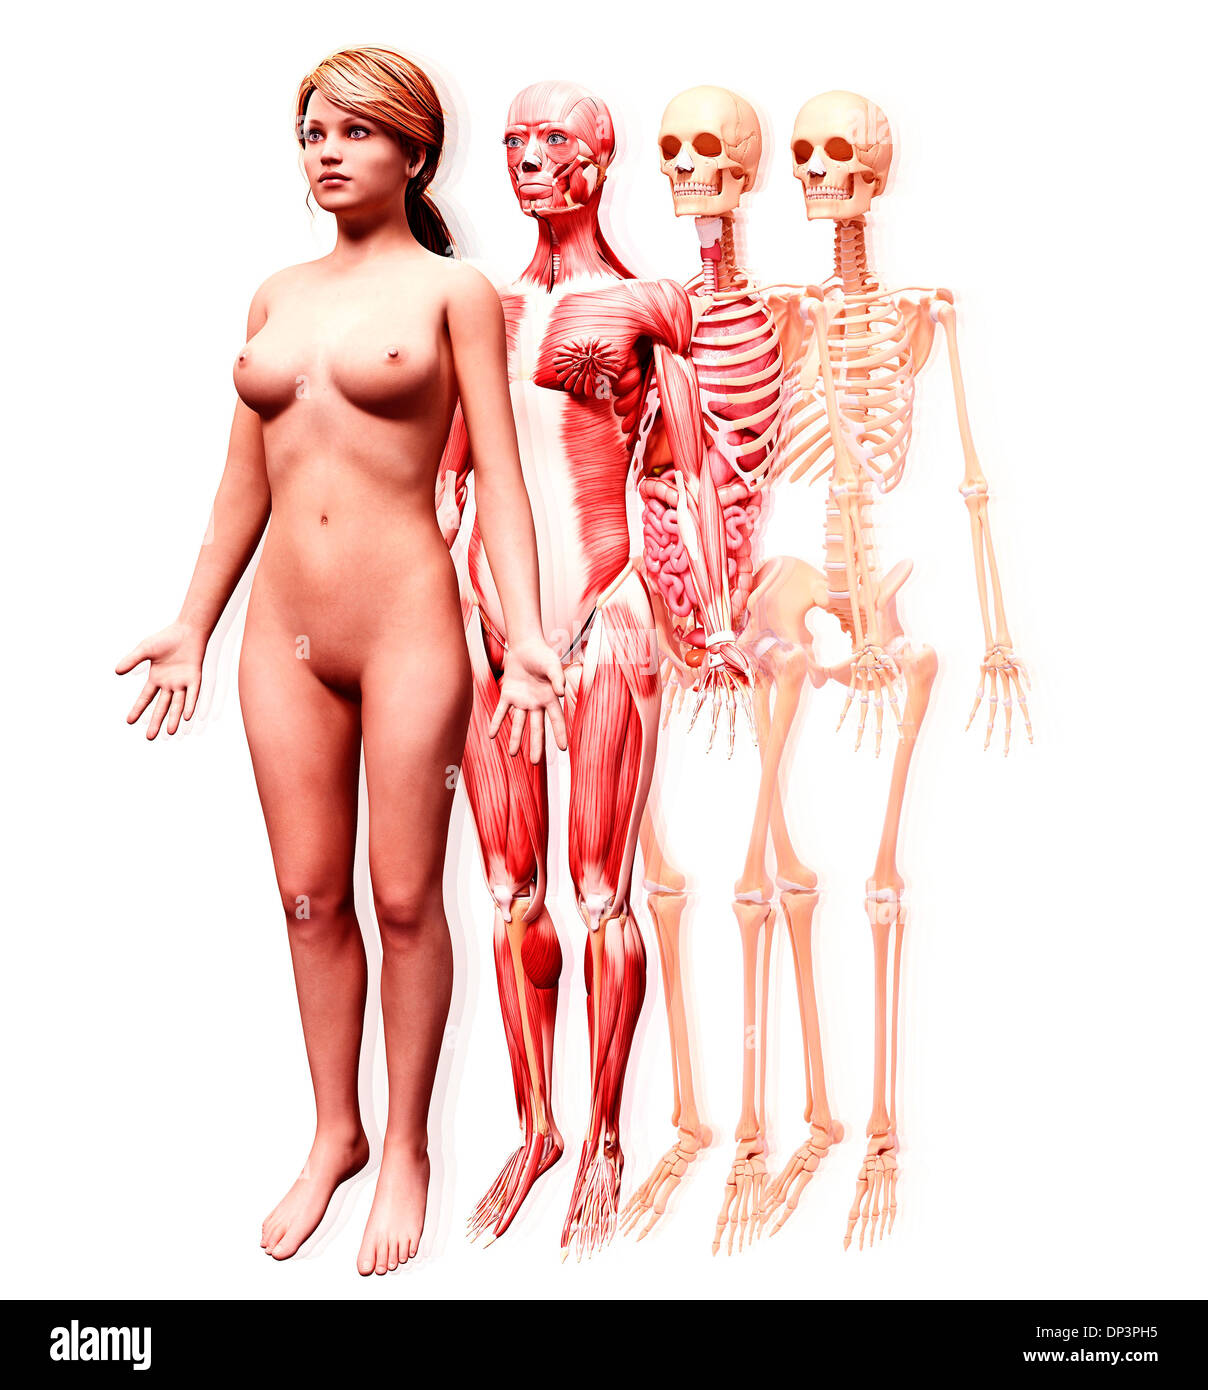

Human Anatomy, artwork Banque D'Imageshttps://www.alamyimages.fr/image-license-details/?v=1https://www.alamyimages.fr/photo-image-human-anatomy-artwork-55444709.html

Human Anatomy, artwork Banque D'Imageshttps://www.alamyimages.fr/image-license-details/?v=1https://www.alamyimages.fr/photo-image-human-anatomy-artwork-55444709.htmlRFD65M85–Human Anatomy, artwork